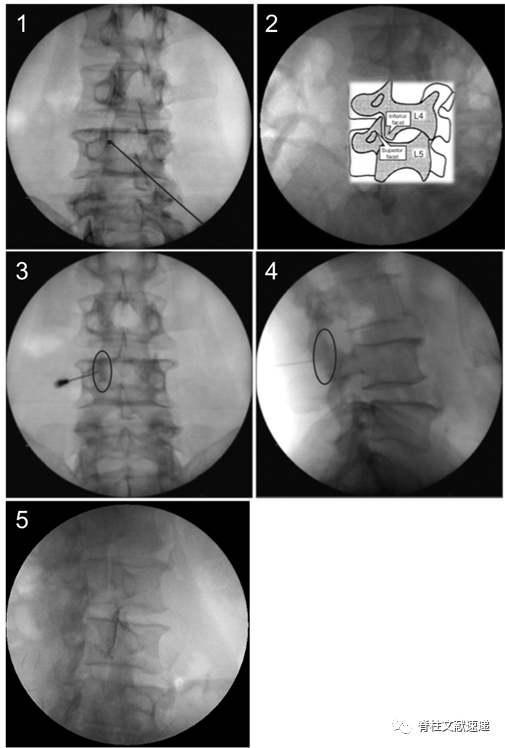

5.2 旋转C臂至斜位,透视出“Scottie dog”小狗影像。(上图1、2)

5.3 穿刺靶点是上关节突内侧缘,穿刺突破关节囊时会有轻微落空感,阻力消失。(上图3、4)

5.4 注入0.2ml造影剂确认关节间隙,然后注入局麻药物。(上图5)